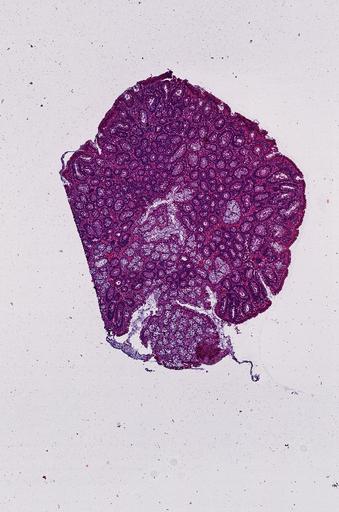

High‑resolution three‑dimensional (3D) tissue atlases promise to redefine how we study cellular architecture‑function relationships in human tissues. Large-scale consortia such as the Human Bimolecular Atlas Program (HuBMAP) systematically build detailed 3D organ maps by profiling serial tissue sections with single-cell spatial technologies. However, an accurate and efficient reconstruction method that can handle atlas-scale datasets remains elusive. We introduce Space-map, an open-source method that integrates single‑cell coordinates with optional histological image features to assemble serial sections into 3D models. Space‑map combines multi‑scale feature matching with large‑deformation diffeomorphic metric mapping, delivering global reconstructions while preserving local micro‑anatomy. To demonstrate the capability of Space-map, we generated a serially sectioned spatial transcriptomics (Xenium, ~2.9M cells) dataset and a spatial proteomics dataset (CODEX, ~2.4M cells). Applying Space-map to these single-cell spatial maps, we built three 3D models for both diseased (colon polyp) and reference colon tissues. These high-resolution 3D models showcase the intricate structure of the human colon across different states. Space-map is fast and highly efficient. We demonstrated its performance and accuracy using in‑house and public datasets. The result shows that Space‑map is 10 times faster and ~2‑fold more accurate than PASTE and STalign, making 3D atlas reconstruction more accessible. Our study provides a new robust and user-friendly software available at https://github.com/a12910/spacemap that can be easily applied for constructing molecular 3D tissue maps of human organs at single-cell resolution.